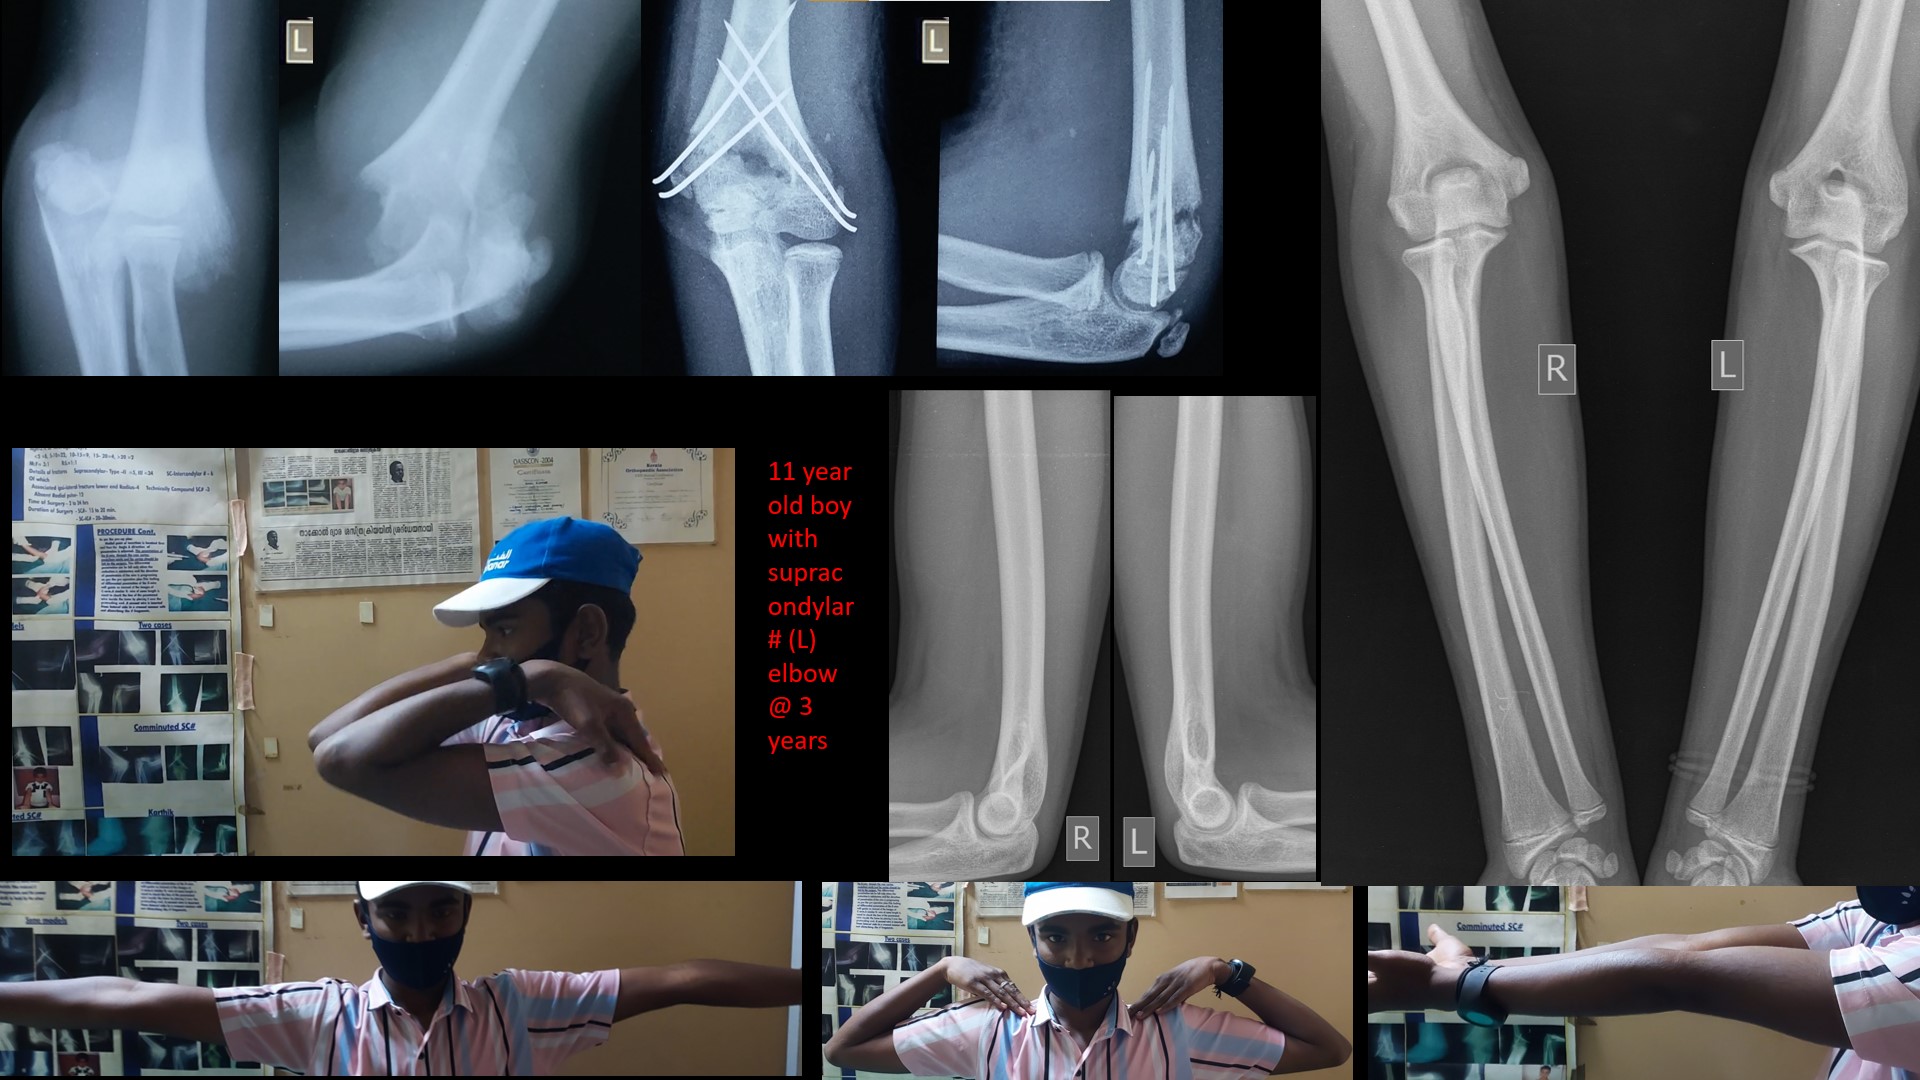

SUPRACONDYLAR #